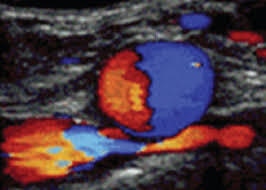

Avalia a aorta e as artérias ilíacas e fluxo sanguíneo. É indicado, principalmente, na avaliação dos aneurismas de aorta (dilatações) assintomáticos e normalmente relacionados à aterosclerose, fumo e doenças cardíacas. Também é recomendado para a avaliação de dissecções e obstruções arteriais, assim como no controle posterior ao tratamento clínico ou cirúrgico dos aneurismas. Esse exame também avalia os stents.